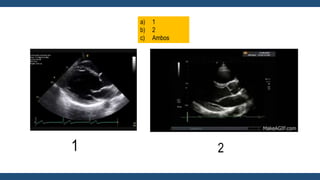

Ecocardiograma

• Permite el Dx de Estenosis Mitral

• Evalúa la severidad (Gradientes, Orificio valvular, Presión en arteria

pulmonar).

• Ayuda al Dx de lesiones Valvulares acompañantes.

• Valora el Tamaño, condiciones y función del VD (Afectado por aumento

de presiones pulmonares).

Guadalajara, J. F. (2012). Cardiología. CDMX: Mendez Editores.

a) 1

b) 2

c) Ambos

1 2

Eje Corto

El área de la válvula mitral se mide

mediante planimetría directa de eje corto.

Ecocardiograma • Permite elDx de Estenosis Mitral • Evalúa la severidad (Gradientes, Orificio valvular, Presión en arteria pulmonar). • Ayuda al Dx de lesiones Valvulares acompañantes. • Valora el Tamaño, condiciones y función del VD (Afectado por aumento de presiones pulmonares). Guadalajara, J. F. (2012). Cardiología. CDMX: Mendez Editores.

a) 1 b) 2 c)Ambos 1 2